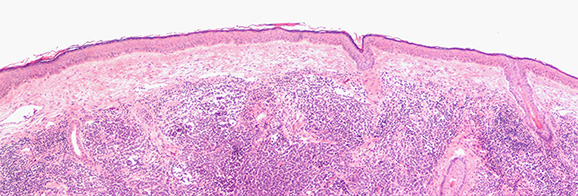

Incyte ist in den Bereichen der hämatologisch-onkologischen und dermatologischen Erkrankungen aktiv. Für relevante Hintergrundinformationen zu diesen Indikationen klicken Sie auf eine der folgenden Kacheln.